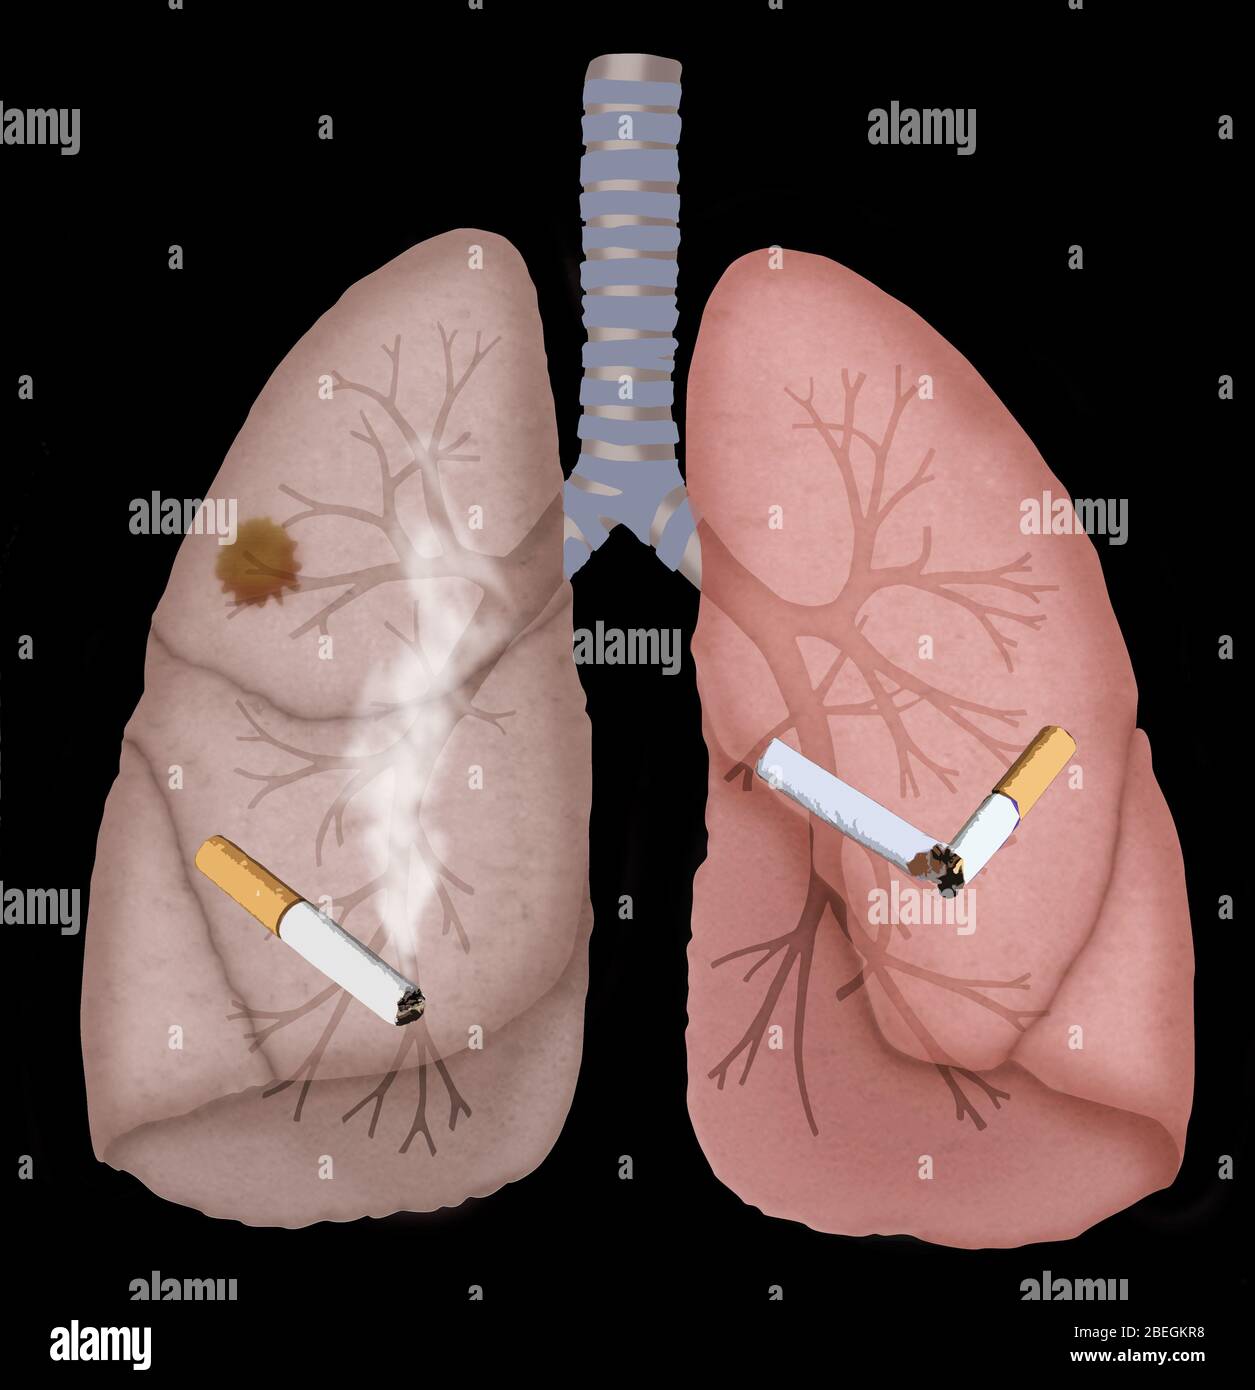

Фото Легких После Вейпа 107 фотографий